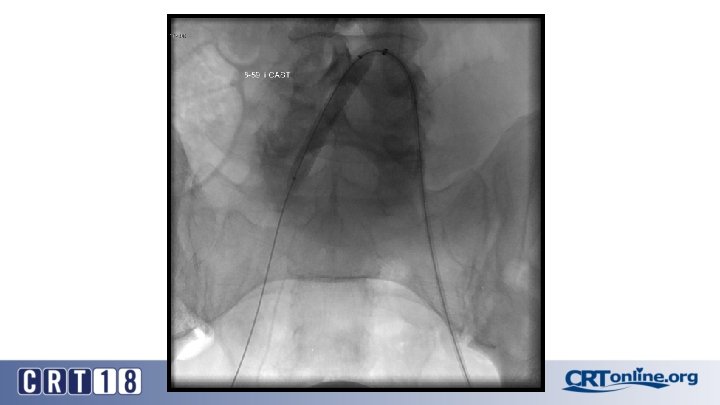

CS Compared to BMS in iliac occlusion • 2009 and December 2015, 128 iliac artery occlusions were stented • A CS was implanted in 78 iliac arteries (61%) and a BMS in 50 (49%) • After propensity score matching (lesion site and length separated and associated femoropopliteal disease included) (47 for each group). • Technical success was 98% • Complication rates same: 12% vs. 12%, p = 1. 0 • 30 day mortality rates same: 2% vs. 2%, p = 1. 0 Piazza M, et al. Outcomes of polytetrafluoroethylene-covered stent versus bare-metal stent in the primary treatment of severe iliac artery obstructive lesions. J Vasc Surg. 2015; 62(5): 1210 -8.

CS superior to BMS, in the right setting • At 36 months (average 23 ± 17) overall primary patency only approached significance: 87% vs. 66%, p =. 06 • For TASC D, CS: 88% vs. BMS: 54% (p =. 03) • Patency was in favor of CSs for occlusions > 3. 5 cm in length (p =. 04), total lesion length > 6 cm (p =. 04), and occlusion with calcification > 75% of the arterial wall circumference (p =. 01) • Kissing stent patency also superior with CS